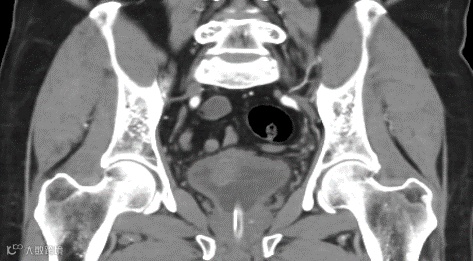

▲患者影像资料

本次手术患者60岁男性,以“血尿2月余”为主诉入院,经增强CT检查及病理会诊确诊为高级别浸润性尿路上皮癌,浸润固有层。经过仔细评估并结合患者病情及意愿,郑大一附院泌尿外科团队制定腹腔镜下膀胱根治性切除、盆腔淋巴结清扫+回肠代膀胱手术方案,并由张雪培教授远程实施。